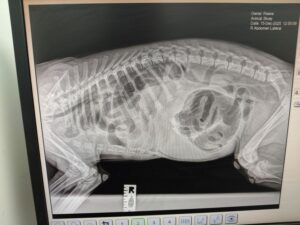

Even though blood tests did not show anything, senior vet Lloyd Groves was concerned about a possible blockage in the bowel so carried out a scan of Bluey’s abdomen and took X-rays of his chest and abdomen, right.

To his surprise, the X-rays showed a diaphragmatic hernia, which has probably been present since birth, and that was causing the super-cute Lurcher considerable pain, requiring immediate advanced surgery – a high risk for such a young puppy.